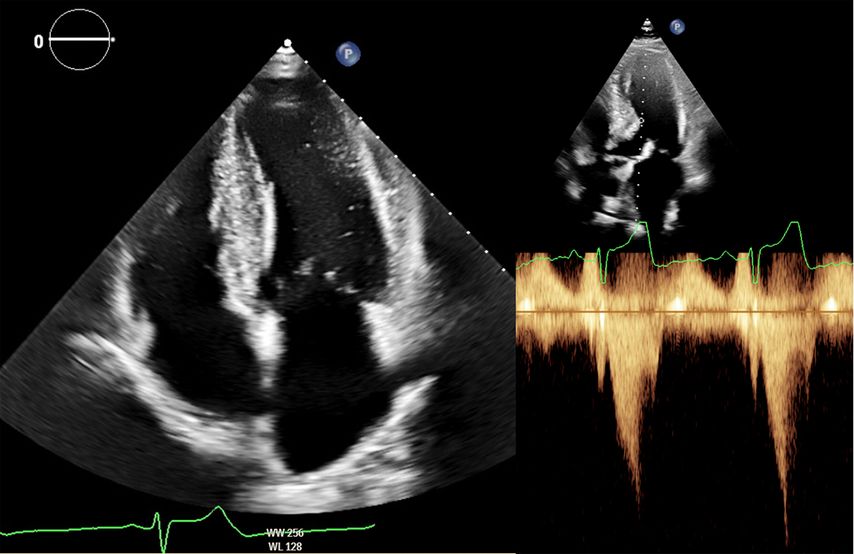

Zur echokardiografischen Beurteilung einer LVH wird üblicherweise der Durchmesser des intraventrikulären Septums und der Posterolateralwand herangezogen. Hier gelten bereits Werte >9mm bei Frauen und >10mm bei Männern als verdickt. Methodenbedingt werden die Wanddicken in der Echokardiografie jedoch häufig überschätzt (Abb.2). Definiert ist die LVH deshalb über die myokardiale Masse bezogen auf die Körperoberfläche (BSA; w: ≤95g/BSA; m: ≤115g/BSA), einen Parameter, der in der klinischen Praxis kaum verwendet wird.8

Abb. 2: Echokardiografie bei HOCM mit 4-Kammer-Blick (links) und Obstruktion im Ausflusstrakt (rechts)

Dennoch ist die Echokardiografie aufgrund der niederschwelligen Verfügbarkeit als erste Untersuchungsmodalität und zur Verlaufsbeurteilung nicht wegzudenken. Mit der Ejektionsfraktion, der Vorhofgröße und der Beurteilung der diastolischen Funktion können prognostisch wichtige Parameter erhoben werden. Ein „apical sparing“ in der Analyse des myokardialen Strains oder der Aspekt eines „granular sparkling“ kann einen Verdacht auf kardiale Amyloidose begründen (Abb.3). Jede echokardiografische Untersuchung wegen des Verdachts auf LVH sollte außerdem eine Bestimmung des LVOT-Gradienten inkl. Valsalva-Manöver beinhalten (Abb.2).